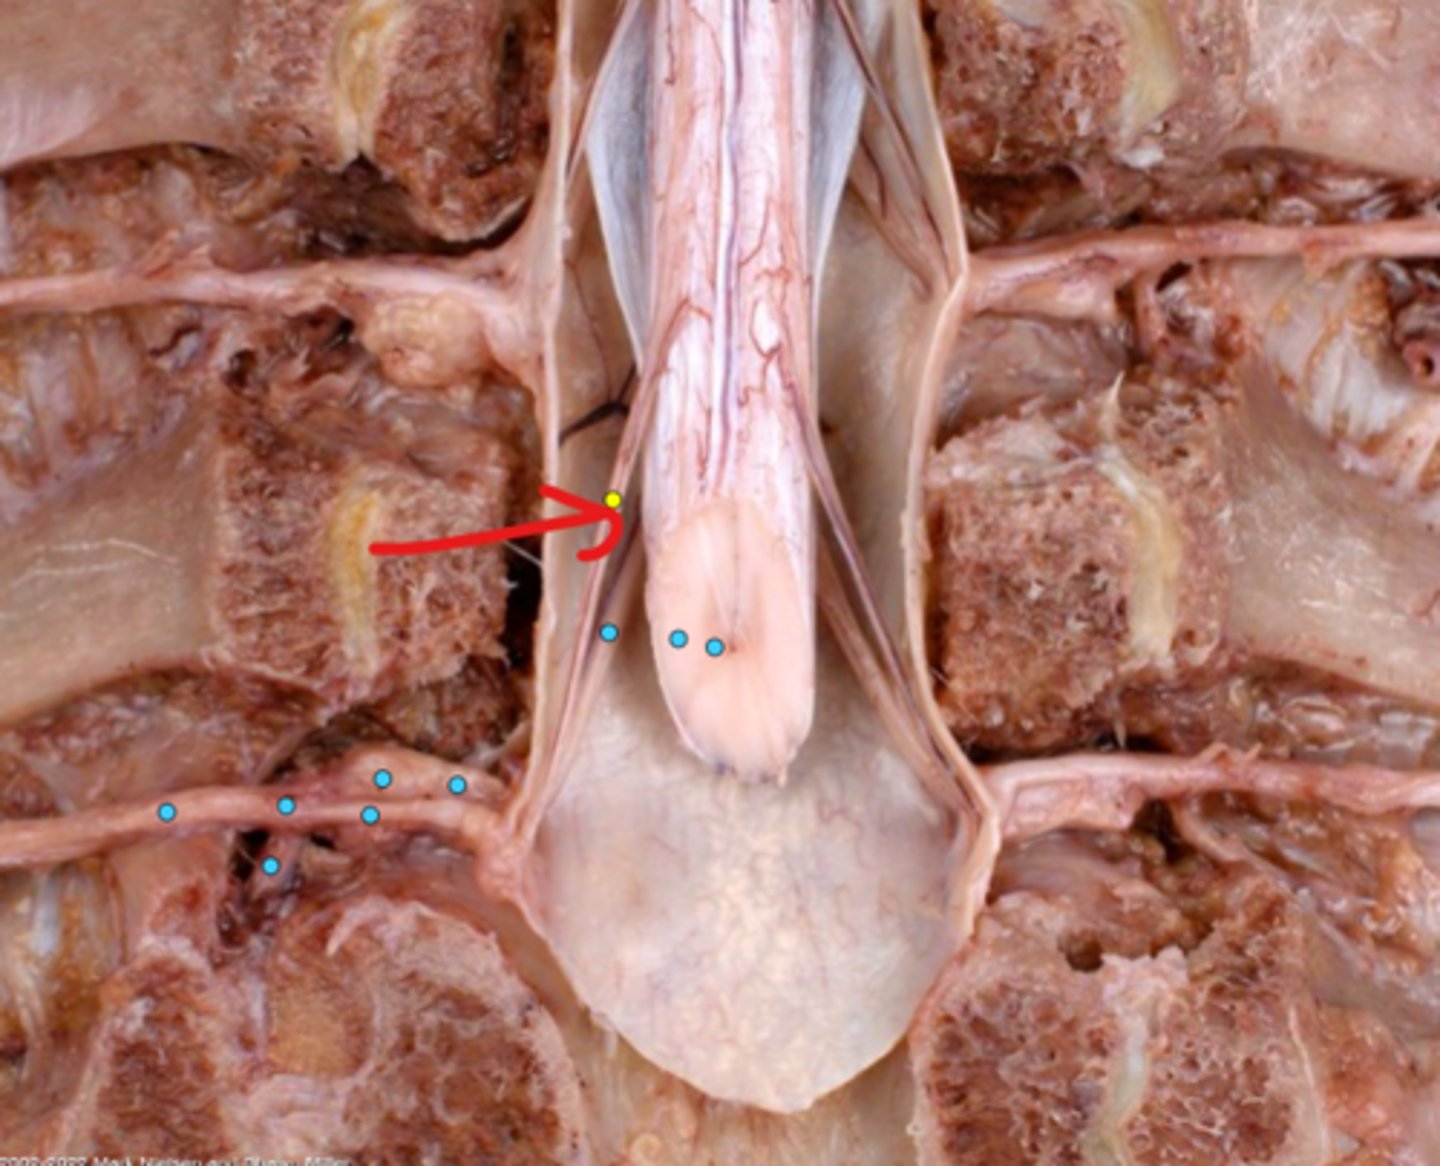

Intercostal nerve

Communicating ramus

Sympathetic trunk ganglion

Sympathetic trunk

Lesser splanchnic nerves

Greater splanchnic nerve

Anterior (ventral) ramus

Spinal nerve trunk

Posterior (dorsal) ramus

Spinal ganglion

Anterior (ventral) root

Posterior (dorsal) root

Anterior (ventral) rootlets

Posterior (dorsal) rootlets

White matter

Gray matter

Posterior (dorsal) rootlets

Anterior (ventral) rootlets

Spinal cord